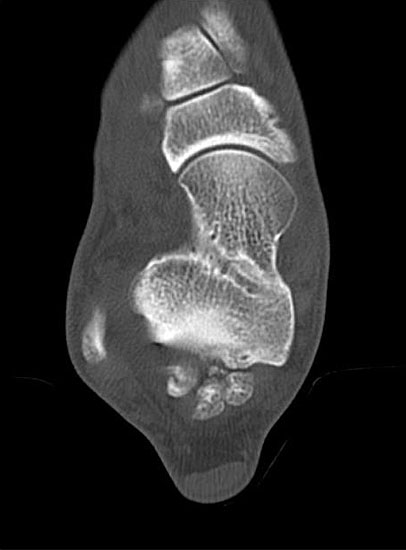

Abbildung Nr. 19-22

Knochenresektat sowie präoperatives CT (Sagittal- und Transversalebene) und intraoperative Bildwandlerkontrolle im seitlichen Strahlengang nach arthroskopischer Entfernung multipler Ossikel am dorsalen OSG/USG.